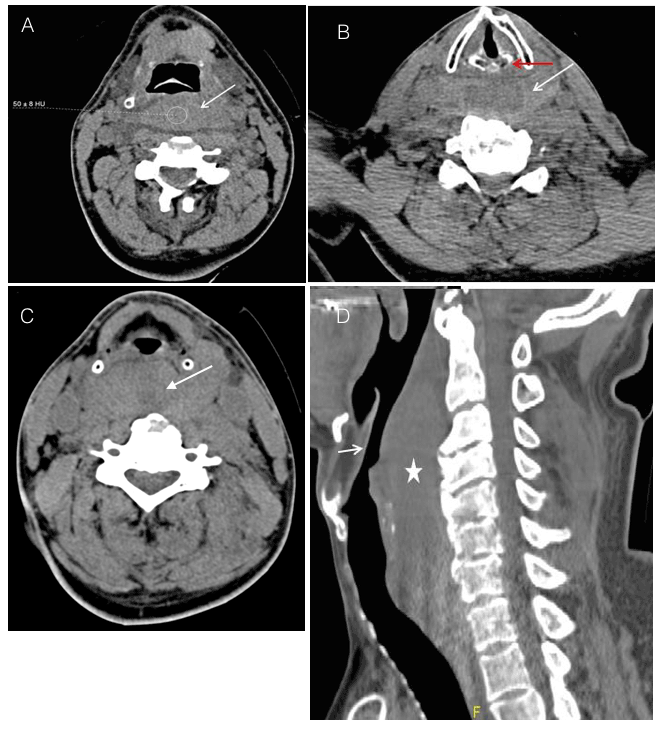

He was conscious but incoherent possibly as a result of alcohol intoxication or due to blood loss. He was resuscitated as per the ATLS® protocol and shifted for PAN CT (Trauma protocol). CT revealed a stable fracture of the C5-C6 transverse processes, with a  prevertebral hematoma extending from C1 to C5 vertebral level (Figure 1). The patient was monitored throughout with no signs of vital deterioration.

Figure 1. A. Axial unenhanced CT neck at the level of the epiglottis shows prevertebral/retropharyngeal high density (ROI density of 50 +- 8 Hounsfield Unit, white arrow) signifying hematoma.

B. Axial unenhanced CT neck at the level of the vocal cords and arytenoid cartilage (red arrow) shows prevertebral / retropharyngeal high density (white arrow) signifying hematoma.

C. Axial unenhanced CT neck at the level of the hypopharynx showing prevertebral/retropharyngeal high density (white arrow) signifying hematoma displacing the airway anteriorly.

D. Sagittal unenhanced CT neck (right lower corner) shows prevertebral/retropharyngeal high density (white star) signifying hematoma. This is causing significant narrowing of the airway (short white arrow).